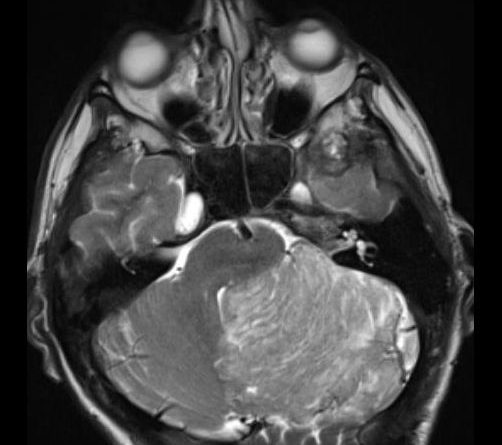

24 yaş, E

Baş ağrısı

Lhermitte duclos

Lhermitte-Duclos hastalığı (Dysplastic cerebellar gangliocytoma)

Dysplastic cerebellar gangliocytoma(Lhermitte-Duclos hastalığı)

Lhermitte-Duclos hastalığı

Displastik serebellar gangliositoma